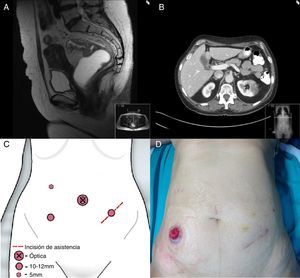

A) RM de pelvis donde se observa tumoración de recto que no sobrepasa la muscular propia. B) Imagen de TC axial de abdomen en la que se muestra masa renal izquierda de 5cm.C) Ubicación de los trocares utilizada para la realización de la nefrectomÃa y resección anterior baja. D) Imagen del abdomen de la paciente con la ileostomÃa de protección.

Mujer de 57 años en estudio por anemia ferropénica. La colonoscopia evidencia tumoración de recto a 7cm del margen anal, cuya estadificación local por RMN de pelvis (fig. 1A) y ecografÃa endorrectal es de T2N0. La TC abdominal muestra una tumoración en riñón izquierdo sugestiva de neoplasia primaria (fig. 1B). En coordinación con el servicio de urologÃa se realiza abordaje laparoscópico con 4 puertas situadas para servir a ambos procedimientos (fig. 1C), colocando a la paciente en posición de Lloyd-Davis. Se comienza por la movilización completa del ángulo esplénico, dejando la fosa renal libre para realizar la nefrectomÃa reglada y extracción en bolsa por incisión de 6cm en flanco izquierdo. Completamos la resección anterior baja, realizando una anastomosis término-terminal mecánica y una ileostomÃa de protección (fig. 1D). La paciente evoluciona favorablemente y es alta al 5.° dÃa del postoperatorio. El estudio anatomopatológico informa de mesorrecto Ãntegro con margen distal a 2,8cm y margen circunferencial libre, con 18 ganglios aislados, todos libres de infiltración neoplásica y tumor de células claras de riñón TNMpT3.